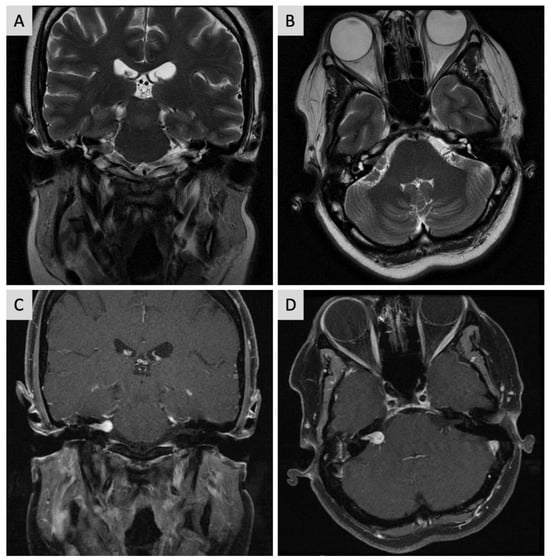

2. Case Report